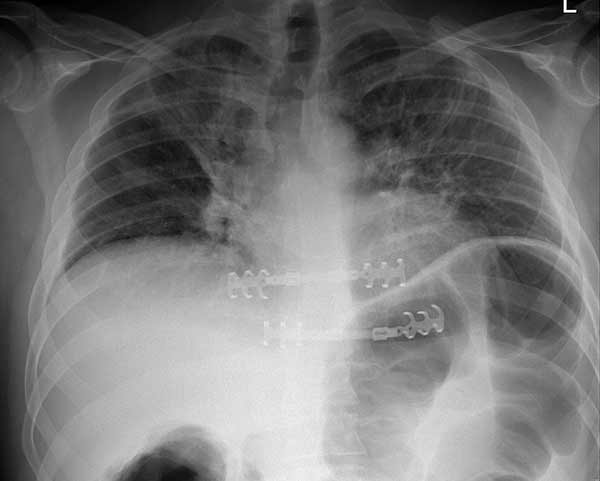

- Chest wall resection for malignancy (Figures 4-5)

| Figure 4: Model showing application in chest wall resection. | Figure 5: Postoperative chest x-ray showing the implants |